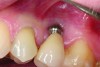

Implant related complications may be classified as minor, intermediate, major reversible/nonreversible, or major nonreversible. For example, a simple complication like a fractured abutment screw is usually considered a minor complication. It usually can be corrected with minimal cost, time, pain, and inconvenience. Treatment may be more involved for an intermediate complication such as a fractured implant (Figure 1). Up the severity scale are major complications, such as when an implant migrates into the sinus2 (Figure 2), or is exposed by mucosa and bone loss and visible to the patient a year after restoration (Figure 3 and Figure 4). Major complications may cause irreversible damage and/or require multiple procedures to try to make the patient “whole,” adding cost, time, pain, and surgeries (Figure 5 and Figure 6), and the patient may or may not receive the original restoration.

An implant that migrated into the sinus may be considered a major reversible complication.

Figure 2